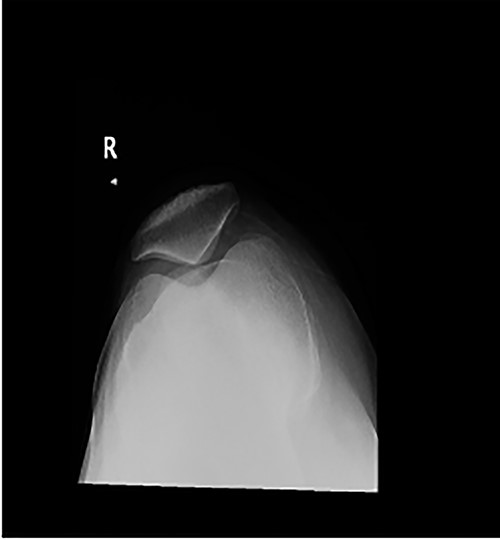

Long weight-bearing knee radiographs showed severe osteoarthritic changes, 18° knee genuvarum and extension deformity of the left distal femur (Fig. 2). Skyline view showed severe arthritic changes (Fig. 3).